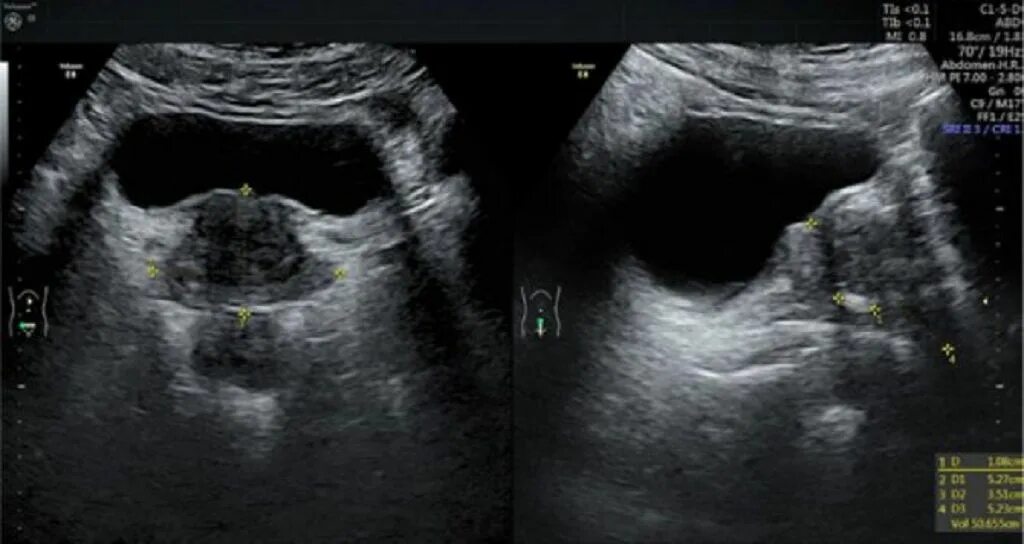

Нарезка простата